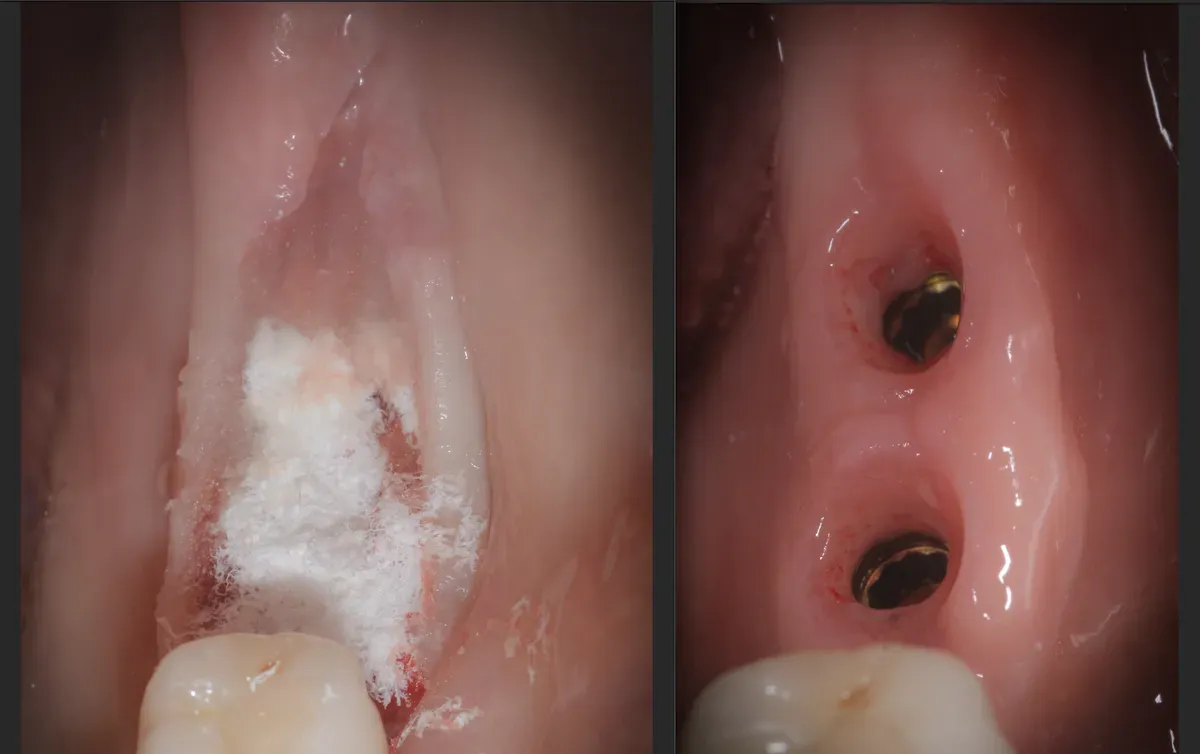

Illustrazione scientifica che rappresenta una sezione del tessuto cheratinizzato, evidenziando la struttura cellulare e le caratteristiche morfologiche, utile per la discussione sulla rigenerazione osteo-mucosa e l

Immagine tratta da pagina 109 di “Surgery; its theory and practice” (1896). Illustra il fronte di guarigione nel processo descritto nell’articolo. Le cellule del tessuto di granulazione riparativo colmano progressivamente la zona centrale.

La Gingival Open-Wound Technique è una tecnica per aumentare il tessuto cheratinizzato intorno agli impianti dentali sfruttando la guarigione per seconda intenzione. Non utilizza innesti autologhi o biomateriali, ma sfrutta la capacità rigenerativa naturale dei tessuti. Noi la applichiamo da 26 anni con variazioni tecniche specifiche.

Assolutamente sì, se ben eseguita. Richiede: protezione dalla contaminazione batterica, presenza di tessuto cheratinizzato (anche minima), mantenimento dello spazio, stabilizzazione dei lembi. I risultati a 5-10 anni nelle nostre pubblicazioni dimostrano predicibilità e stabilità eccellenti. La chiave è la selezione del caso e la tecnica corretta.